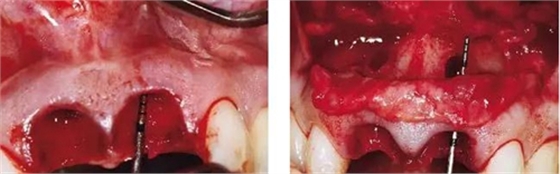

圖2、翻開全厚瓣可見明顯的牙根縱裂,唇側骨板2/3受到累及而缺損。

圖3、拔牙后看到更大范圍的骨缺損,并且缺損導致上頜側切牙根尖牙骨質暴露,繼而存在術后由于軟硬組織退縮而帶來的美學風險。

圖4、植入的種植體,初始穩(wěn)定性很好,由于骨缺損范圍大,選擇潛入式愈合。

圖5、種植體完全位于拔牙窩骨壁包圍的范圍內,距離唇側骨板至少2mm。